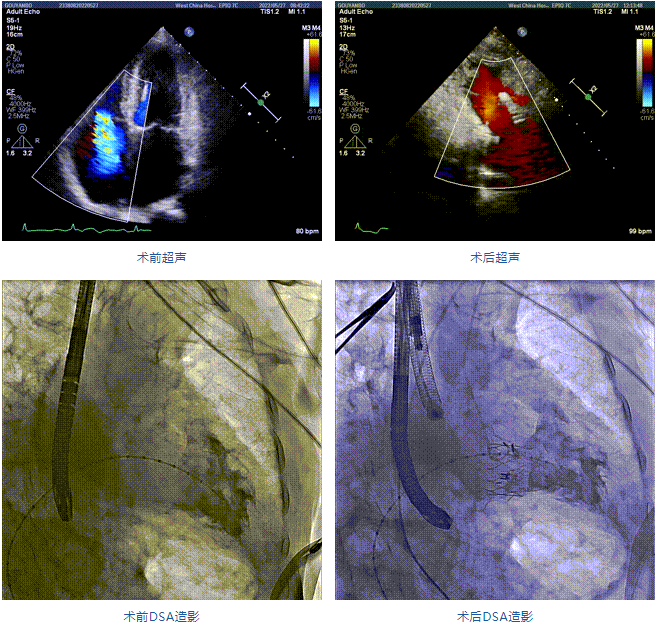

患者為89歲高齡男性,罹患三尖瓣反流多年,近期癥狀明顯加重,經(jīng)過充分的藥物治療后仍然存在嚴(yán)重心力衰竭。通過純介入方式實(shí)施三尖瓣置換,使這位超高齡的老人以最小的代價(jià)獲得了有效的治療。介入治療的效果十分滿意,術(shù)后三尖瓣反流消除,老人迅速恢復(fù),心功能明顯改善。該手術(shù)的成功實(shí)施標(biāo)志著國(guó)內(nèi)經(jīng)導(dǎo)管三尖瓣置換進(jìn)入純介入時(shí)代。

89歲男性。術(shù)前超聲報(bào)告顯示:雙房增大,左室壁肥厚,主、肺動(dòng)脈增寬,三尖瓣重度反流。

團(tuán)隊(duì)前期經(jīng)過多次討論,制定了周密的手術(shù)策略和預(yù)案。由于患者已是近九旬的超高齡老人,傳統(tǒng)外科開胸手術(shù)風(fēng)險(xiǎn)極高,純介入經(jīng)血管三尖瓣替換能夠明顯減少創(chuàng)傷。術(shù)中陳茂及馮沅教授結(jié)合體表定位在造影指示下精準(zhǔn)穿刺右側(cè)頸靜脈并預(yù)置兩把血管縫合器。成功建立經(jīng)皮血管入路后在食道超聲和DSA的引導(dǎo)下順利完成人工瓣膜植入,術(shù)后超聲和造影顯示人工三尖瓣同軸性良好,瓣架固定牢靠,無反流和瓣周漏,平均跨瓣壓差降為1mmHg。術(shù)畢收緊預(yù)置的血管縫合器縫線完成止血,縫合效果滿意,在手術(shù)室即刻拔除氣管插管。